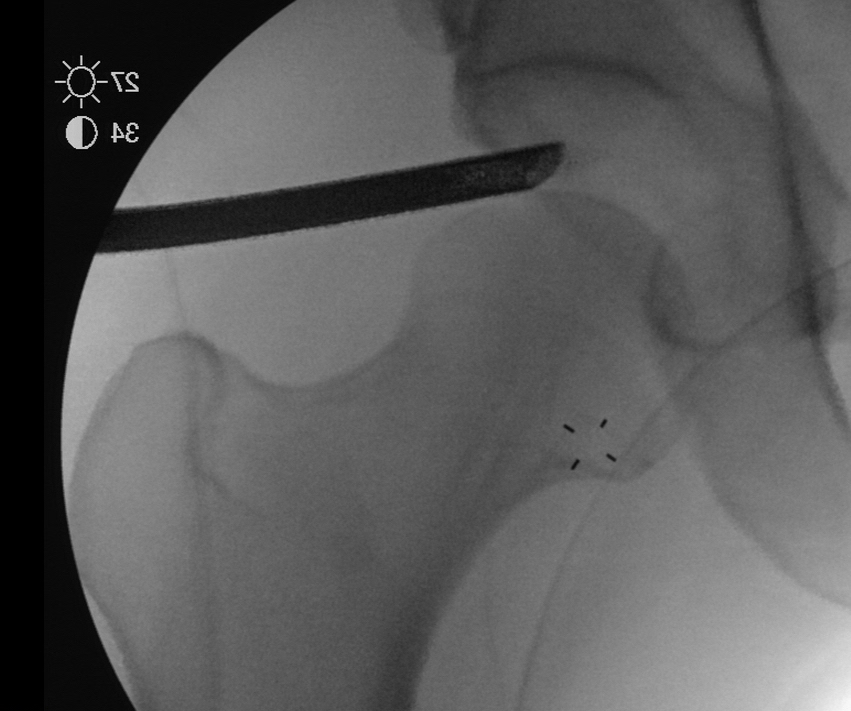

PALA

Insertion of PALA under image intensifier